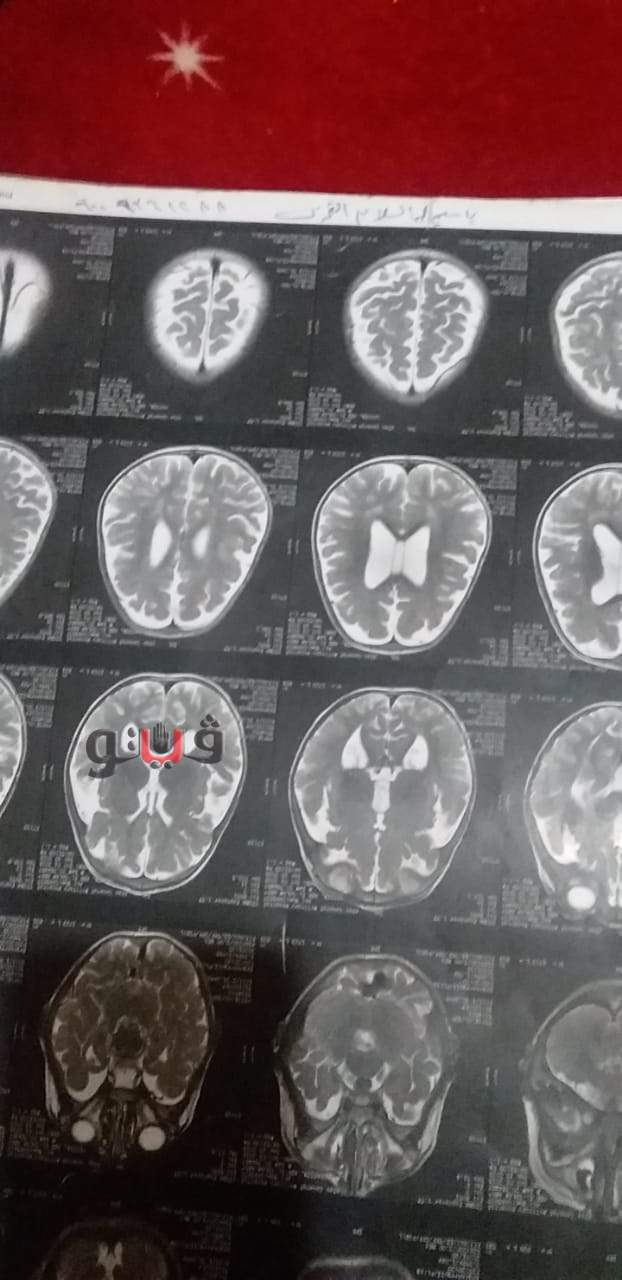

وتابع: "جميع الأطباء الذين ذهبت إليهم أعطوني تشخيصات مختلفة منهم من قال لي إن ابني مصاب بضمور في المخ وتشنجات مستعصية وتأتي بنسبة ضئيلة بين الأطفال، والبعض الآخر بعد فحص الأشعات بالصبغة أخبروني أنه مريض بشلل رباعي وضمور في المخ وزيادة في سائل المخ، ويكتبوا على أدوية لعلاج الكهرباء على المخ، ولكن الأدوية لم تأتي بمفعول".